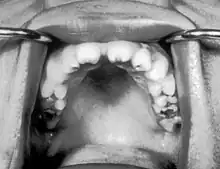

| Notched incisors known as Hutchinson's teeth which are characteristic of congenital syphilis | |

- Blunted upper incisor teeth known as Hutchinson's teeth

A frequently-found group of symptoms is Hutchinson's triad, which consists of Hutchinson's teeth (notched incisors), keratitis and deafness and occurs in 63% of cases.[18]

- Hutchinson's triad, a set of symptoms consisting of deafness, Hutchinson's teeth (centrally notched, widely spaced peg-shaped upper central incisors), and interstitial keratitis (IK), an inflammation of the cornea which can lead to corneal scarring and potential blindness